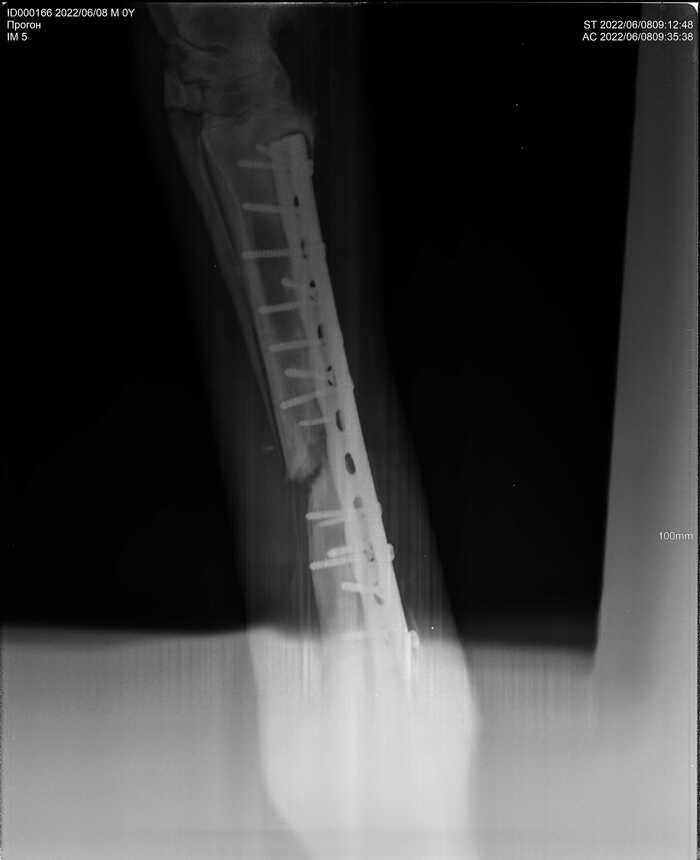

Но несмотря на заметные глазу улучшения, рентгены говорили об обратном. Местные вет врачи, а также многочисленные консультации с лучшими московскими и питерскими клиниками сводились к одному - остеомиелит, проще говоря, кость разрушалась, а не срасталась. На фото рентген спустя 3 месяца после операции

И спустя еще один месяц результат был примерно тот же

С момента операции прошло уже больше 4 месяцев, результата сращивания кости нет, здоровье молодой лошади сильно подорвано антибиотиками, состояние почек можно назвать как "не сегодня, так завтра откажут". Артроз скакательного сустава больной ноги был диагностирован по рентгенам (из-за того, что слишком долго сустав бы зафиксирован гипсом), артроз всех здоровых ножек виден уже снаружи. Не говоря уже о менее значительных изменениях, таких как сутулая спина, зажатые забитые мышцы всего тела, потеря веса